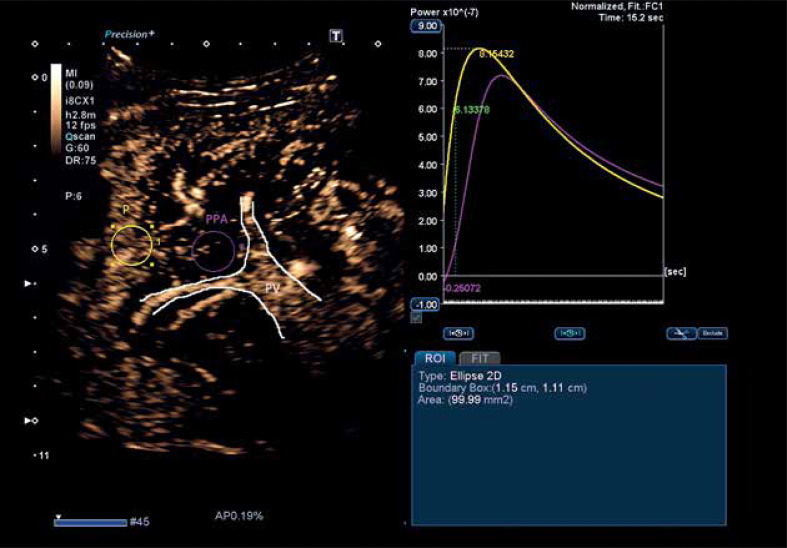

Abstract Image